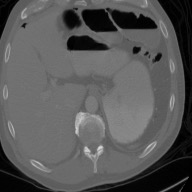

This work presents a novel framework CISFA (Contrastive Image synthesis and Self-supervised Feature Adaptation)that builds on image domain translation and unsupervised feature adaptation for cross-modality biomedical image segmentation. Different from existing works, we use a one-sided generative model and add a weighted patch-wise contrastive loss between sampled patches of the input image and the corresponding synthetic image, which serves as shape constraints. Moreover, we notice that the generated images and input images share similar structural information but are in different modalities. As such, we enforce contrastive losses on the generated images and the input images to train the encoder of a segmentation model to minimize the discrepancy between paired images in the learned embedding space. Compared with existing works that rely on adversarial learning for feature adaptation, such a method enables the encoder to learn domain-independent features in a more explicit way. We extensively evaluate our methods on segmentation tasks containing CT and MRI images for abdominal cavities and whole hearts. Experimental results show that the proposed framework not only outputs synthetic images with less distortion of organ shapes, but also outperforms state-of-the-art domain adaptation methods by a large margin.